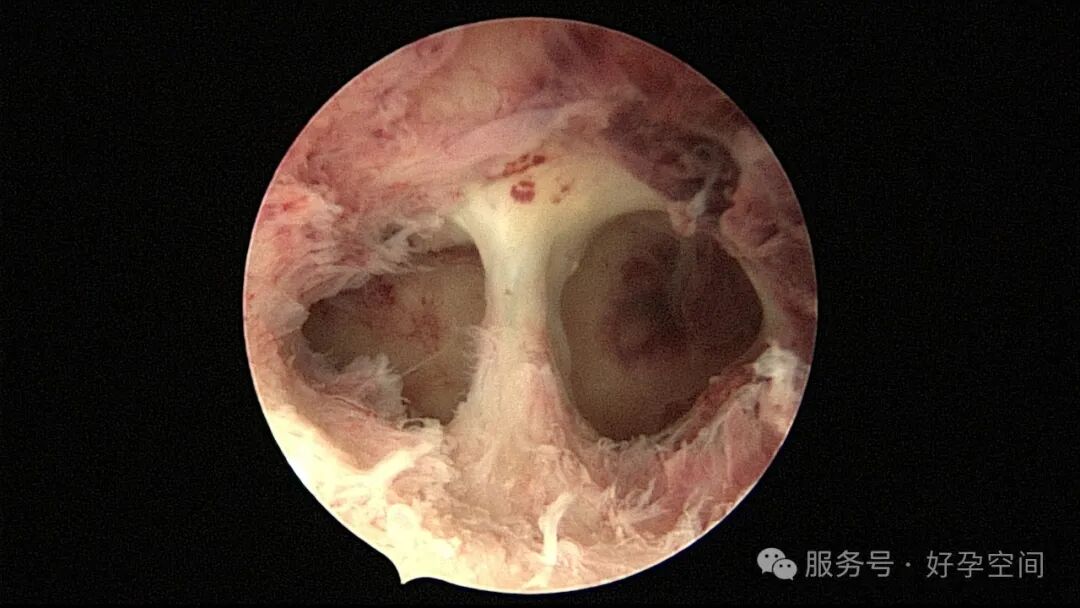

输卵管吻合术后妊娠,稽留流产,清宫术后宫腔粘连,宫腔镜单极电针分粘

分粘后宫腔镜二探,残留少许膜性粘连,镜鞘分粘